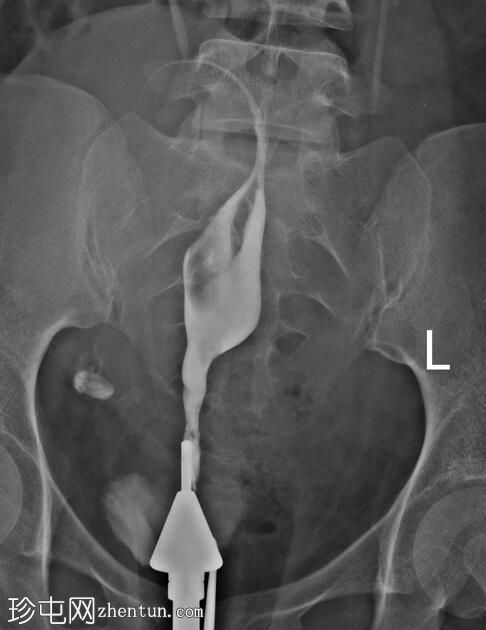

经宫颈管注入造影剂后,子宫腔被充盈。

子宫体位于盆腔中线,呈梭形。

子宫底和子宫体右侧内膜腔可见稳定的充盈缺损,经生理盐水灌注子宫声学造影(未显示)证实为子宫内膜息肉。

可见右侧输卵管走行,蠕动缓慢,未见因输卵管阻塞导致的腹膜溢出。

超声检查(图中未显示)显示,子宫右侧宫底及宫体部存在一个 8 x 9 cm 的壁内浆膜下肌瘤。该肌瘤压迫右侧输卵管的起始部及走行路径,导致其呈垂直走行。

由于输卵管阻塞,左侧输卵管从远端至峡部初级段未显影。